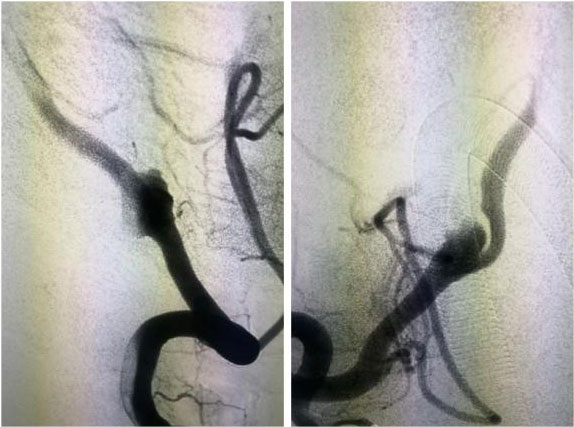

動脈瘤栓塞術(shù):

只需要在病人大腿根部開個小切口,用一根纖細的微導(dǎo)管經(jīng)血管抵達所要治療的動脈瘤部位,向動脈瘤內(nèi)堵塞非常精細的彈簧圈,達到很好治療動脈瘤的目的。是微創(chuàng)外科的方法之一。

▲ 一位動脈瘤患者術(shù)前影像

▲ 術(shù)后,造影顯示動脈瘤無顯影,栓塞成功